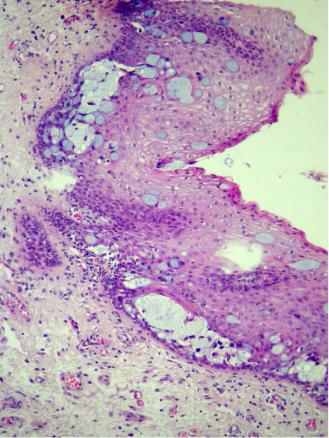

Un homme de 53 ans consulte pour un prurit anal chronique. Divers topiques ne l’ont pas soulagé. L’examen clinique révèle une dermite (fig. 1).